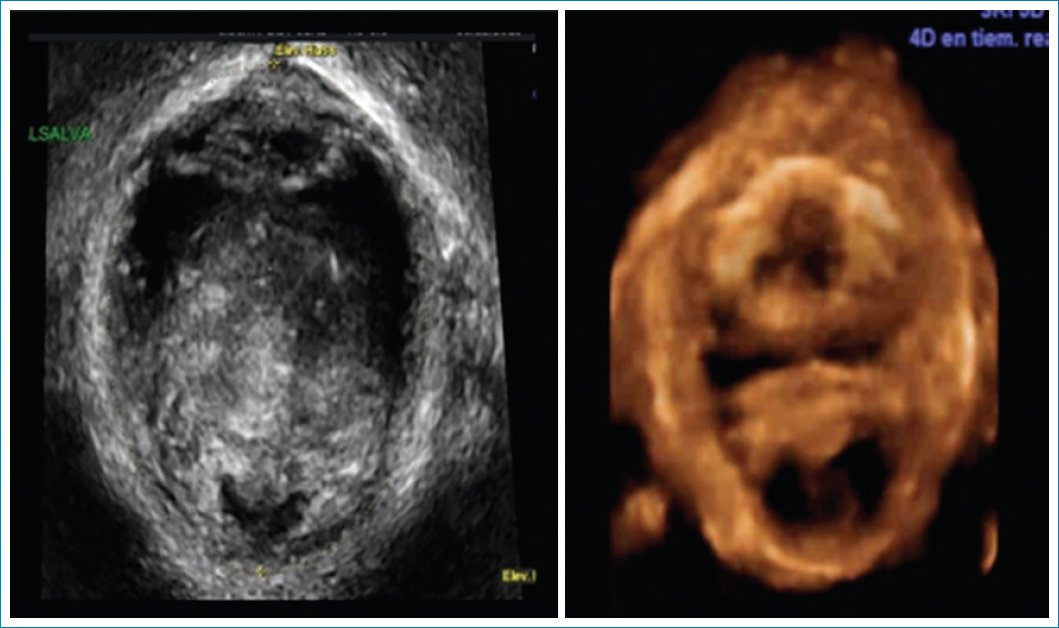

Plano axial 3D-4D7 (Fig. 17)

• – Integridad del haz puborrectal: se evalúa en contracción máxima y se reconstruye en 3D y 4D, se cuantifica el grado de lesión con el ultrasonido tomográfico (Fig. 18).

• – Avulsión del haz puborrectal unilateral o bilateral: la distancia entre la uretra y el músculo puborrectal bilateral no debe ser mayor a 25 mm. Unilateral: asimetría.

• – Microtraumas del elevador del ano: balonización del hiato urogenital en Valsalva. El balonamiento del hiato urogenital se considera cuando es mayor a 25 cc, esto se asocia con prolapso y síntomas de prolapso y mayor probabilidad de recurrencia en reparaciones de rectoceles (Fig. 19).